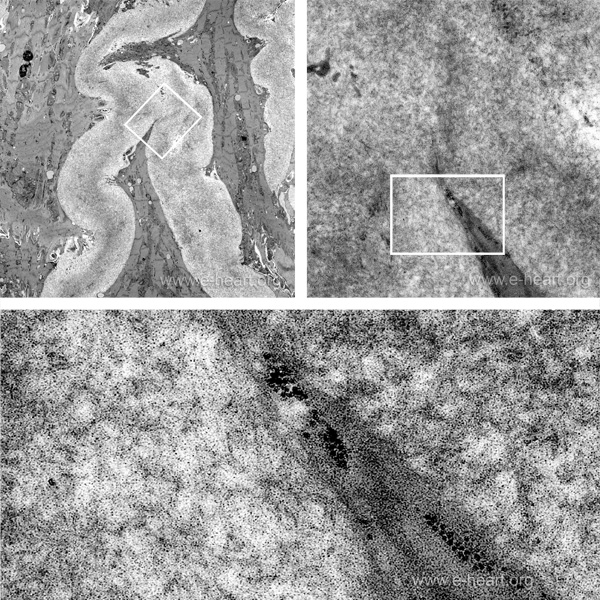

This is a transmission electron micrograph of and endomyocardial biopsy showing perimyocytic deposition of amyloid. The amyloid fibrils, measure and average of 10 nanometers in diameter and form an electron dense deposit. The upper right image shows several cardiac myocytes surrounded by amyloid. The white rectangles show areas of close up which is in turn shown at higher magnification. The 10 nm amyloid fibrils are disctinc thread-like structures.